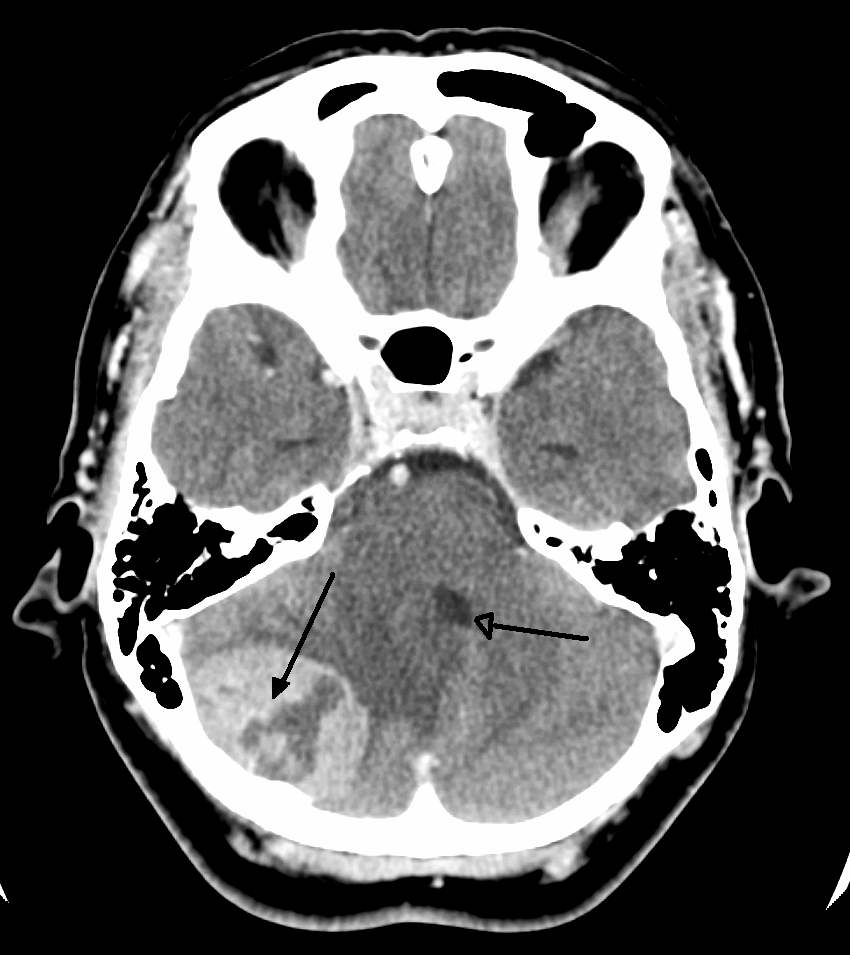

뇌종양은 다른 부위의 종양과는 다르게 진단이 까다롭다. 보통은 방사성 추적자를 이용하여 종양을 촬영하지만, 뇌는 혈액-뇌 장벽(BBB)이라는 막으로 보호되어 있어 추적자가 종양에 도달하기 어렵다. BBB가 파괴되어야 추적자가 뇌종양에 도달할 수 있으며, 이는 자기 공명 영상(MRI)이나 컴퓨터 단층 촬영(CT) 스캔을 통해 확인할 수 있다. 따라서 BBB의 파괴는 악성 교종, 수막종, 뇌 전이의 주요 진단 지표가 된다.[41]

두개인두종은 석회화가 자주 관찰된다. 수막종 또한 종종 석회화를 동반하며, 조영제 사용 CT 또는 MRI에서 균일한 조영 증강 효과를 보인다. 신경교종은 뇌 실질과의 경계가 불분명하며, 조영 시 불균일한 농염상 또는 링 엔핸스먼트가 관찰된다. 그 외에 링 엔핸스먼트가 나타나는 질환으로는 뇌 농양과 전이성 뇌종양이 있다. 악성도가 낮은 신경교종은 일반적으로 조영 효과가 낮다.

5. 1. 영상 검사

의학 영상은 뇌종양 진단에 핵심적인 역할을 한다. 초기에는 침습적이고 위험한 방법들이 사용되었지만, 현재는 비침습적이고 고해상도 기술인 자기 공명 영상(MRI)과 컴퓨터 단층 촬영(CT) 스캔이 주로 사용된다.[42]| 검사 종류 | 설명 | 특징 |

두개인두종은 석회화가 자주 관찰된다. 수막종도 석회화를 동반하며, 조영 증강 컴퓨터 단층 촬영(CT) 또는 자기 공명 영상(MRI)에서 균일한 조영 증강 효과를 보인다. 신경교종은 뇌 실질과의 경계가 불분명하고, 조영 시 불균일한 농염상 또는 링 엔핸스먼트가 관찰된다. 뇌 농양과 전이성 뇌종양도 링 엔핸스먼트가 나타날 수 있다. 악성도가 낮은 신경교종은 조영 효과가 낮다.